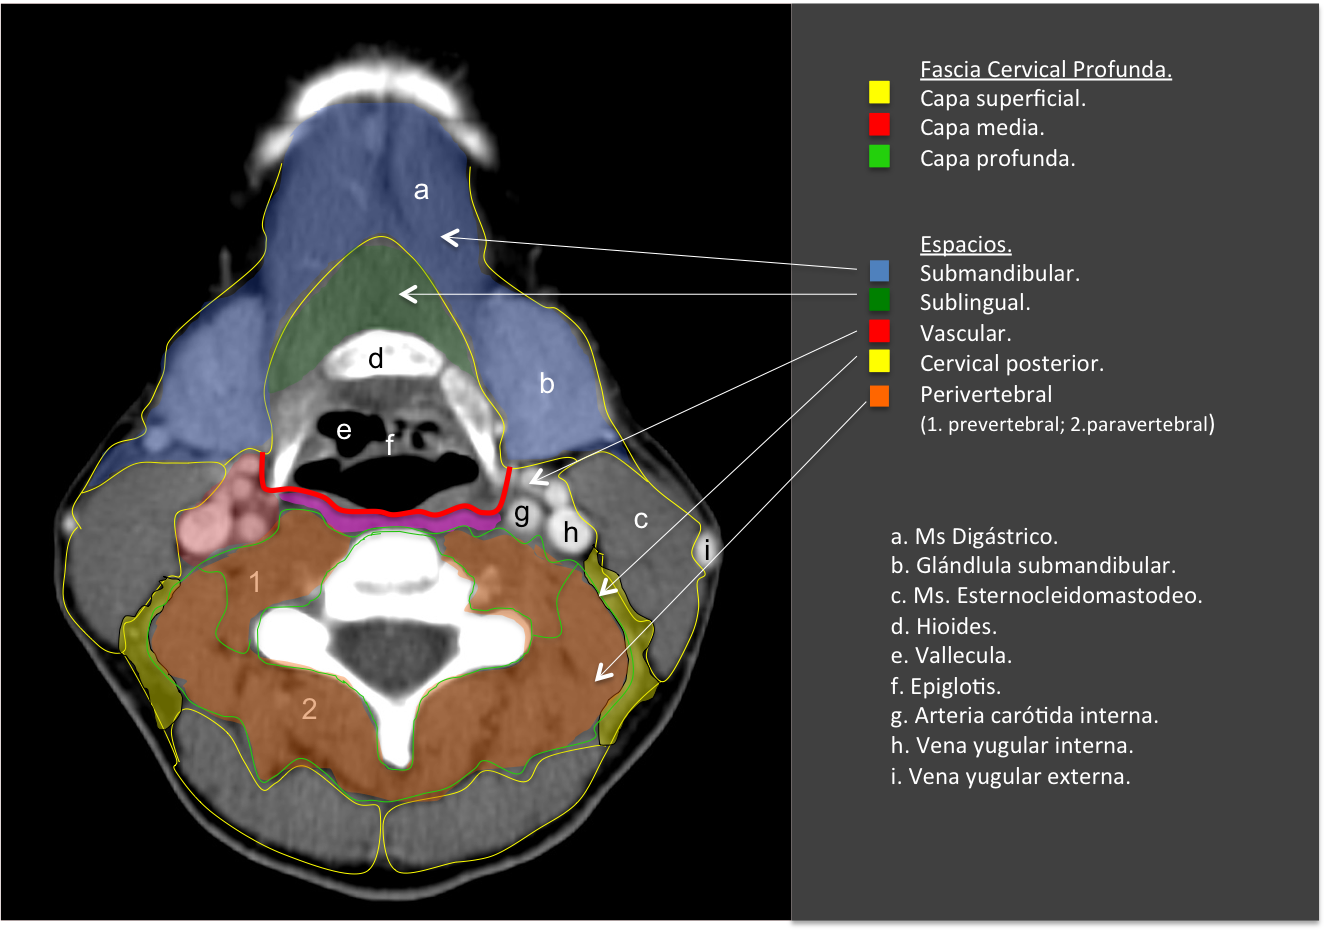

Es esencial conocer la anatomía y relaciones de los espacios cervicales y las fascias. En cuanto a la antomía superfiical, el cuello se puede dividir en:

– Cuello suprahioideo se define como el conjunto de espacios situados en la fascia profunda por encima del hueso hioides: espacio parafaríngeo, espacio de la mucosa faríngea, espacio masticador, espacio parotídeo, espacio vascular (o carotídeo), espacio retrofaríngeo y espacio perivertebral.

– Cuello infrahioideo, por debajo del hueso hiodes. Algunos de estos espacios se continúan hacia arriba (suprahioideo) y/o hacia el mediastino, incluye los espacios: visceral, cervical posterior, vascular, retrofaríngeo y perivertebral.